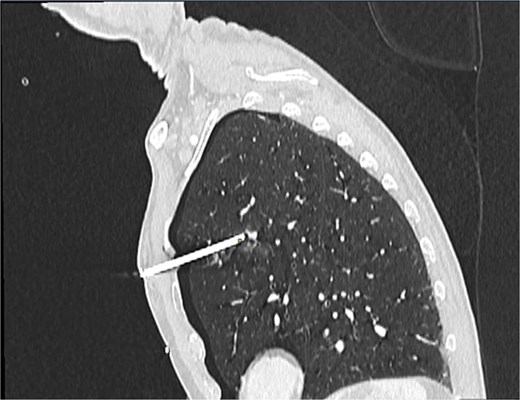

A 60-year-old male smoker presented following accidental discharge of a nail gun into his left chest. On arrival, he was asymptomatic with stable vital signs. Chest radiography showed a 10 cm nail within the left hemithorax and a small apical pneumothorax. Computed tomography (CT) imaging revealed the nail embedded in the upper lobe of the left lung, lying 3 mm from the anterior segmental branch of the pulmonary artery (Figs 1 and 2).

Sagittal CT chest demonstrating nail lodged in the left upper lobe, 3 mm from the anterior segmental branch of the pulmonary artery.